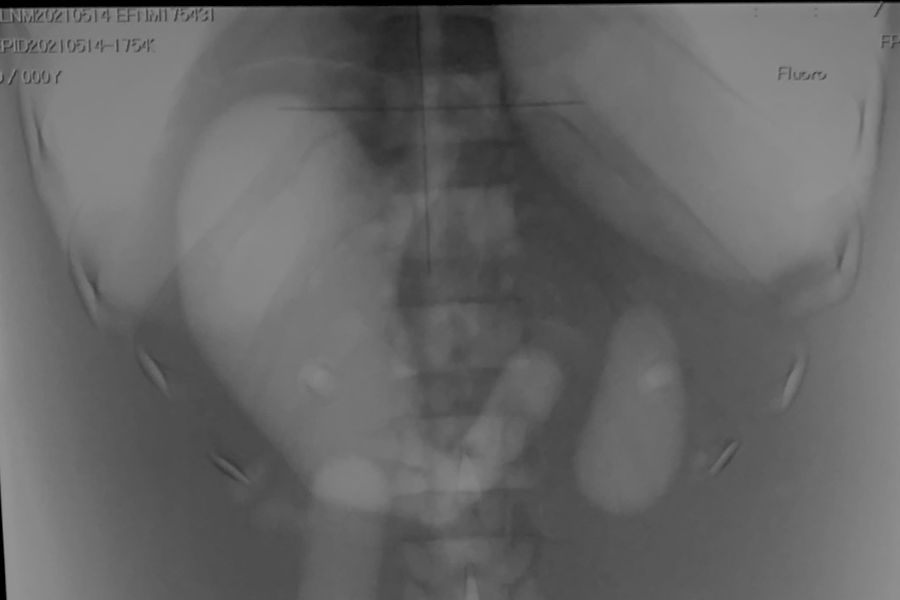

腎結石破砕検査の散乱線空間線量分布の測定 (2022/6/10)

- 施設:藤田医科大学病院デイサージャリー モダリティ:透視 測定器:NanoDot

実験者:西原、富永、間瀬、市川、鈴木、高木、小林

実験系:デイリーサージェリー用のオペ室において腎結石破砕検査の散乱線空間線量分布をジャングルジム法にて測定した。撮影条件は82kV,3mA,60minにて床上100cm、150cmをNanoDot線量計にて測定を行った。